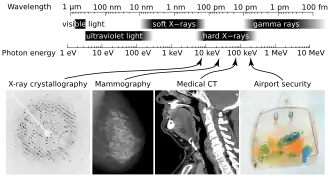

Рентге́новское излуче́ние — электромагнитные волны, энергия фотонов которых лежит на шкале электромагнитных волн между ультрафиолетовым излучением и гамма-излучением (от ~10 эВ до нескольких МэВ), что соответствует длинам волн от ~103 до ~10−2 Å (от ~102 до ~10−3 нм)[1].

Энергетические диапазоны рентгеновского излучения и гамма-излучения перекрываются в широкой области энергий. Оба типа излучения являются электромагнитным излучением и при одинаковой энергии фотонов — эквивалентны. Терминологическое различие лежит в способе возникновения — рентгеновские лучи испускаются при участии электронов (либо связанных в атомах, либо свободных) в то время как гамма-излучение испускается в процессах девозбуждения атомных ядер. Фотоны характеристического (то есть испускаемого при переходах в электронных оболочках атомов) рентгеновского излучения имеют энергию от 10 эВ до 250 кэВ, что соответствует излучению с частотой от 3⋅1016 до 3⋅1019 Гц и длиной волны 0,005—100 нм (общепризнанного определения нижней границы диапазона рентгеновских лучей в шкале длин волн не существует). Мягкое рентгеновское излучение характеризуется наименьшей энергией фотона и частотой излучения (и наибольшей длиной волны), а жёсткое рентгеновское излучение обладает наибольшей энергией фотона и частотой излучения (и наименьшей длиной волны). Жёсткое рентгеновское излучение используется преимущественно в промышленных целях. Условная граница между мягким и жёстким рентгеновским излучением на шкале длин волн находится около 2 Å (≈6 кэВ)[1].

- При помощи рентгеновских лучей можно «просветить» человеческое тело, в результате чего можно получить изображение костей, а в современных приборах и внутренних органов (см. также рентгенография и рентгеноскопия). При этом используется тот факт, что у содержащегося преимущественно в костях элемента кальция (Z = 20) атомный номер гораздо больше, чем атомные номера элементов, из которых состоят мягкие ткани, а именно водорода (Z = 1), углерода (Z = 6), азота (Z = 7), кислорода (Z = 8). Кроме обычных приборов, которые дают двумерную проекцию исследуемого объекта, существуют компьютерные томографы, которые позволяют получать объёмное изображение внутренних органов.

- В материаловедении, кристаллографии, химии и биохимии рентгеновские лучи используются для выяснения структуры веществ на атомном уровне при помощи дифракционного рассеяния рентгеновского излучения на кристаллах (рентгеноструктурный анализ). Известным примером является определение структуры ДНК.

- В аэропортах активно применяются рентгенотелевизионные интроскопы, позволяющие просматривать содержимое ручной клади и багажа в целях визуального обнаружения на экране монитора предметов, представляющих опасность.